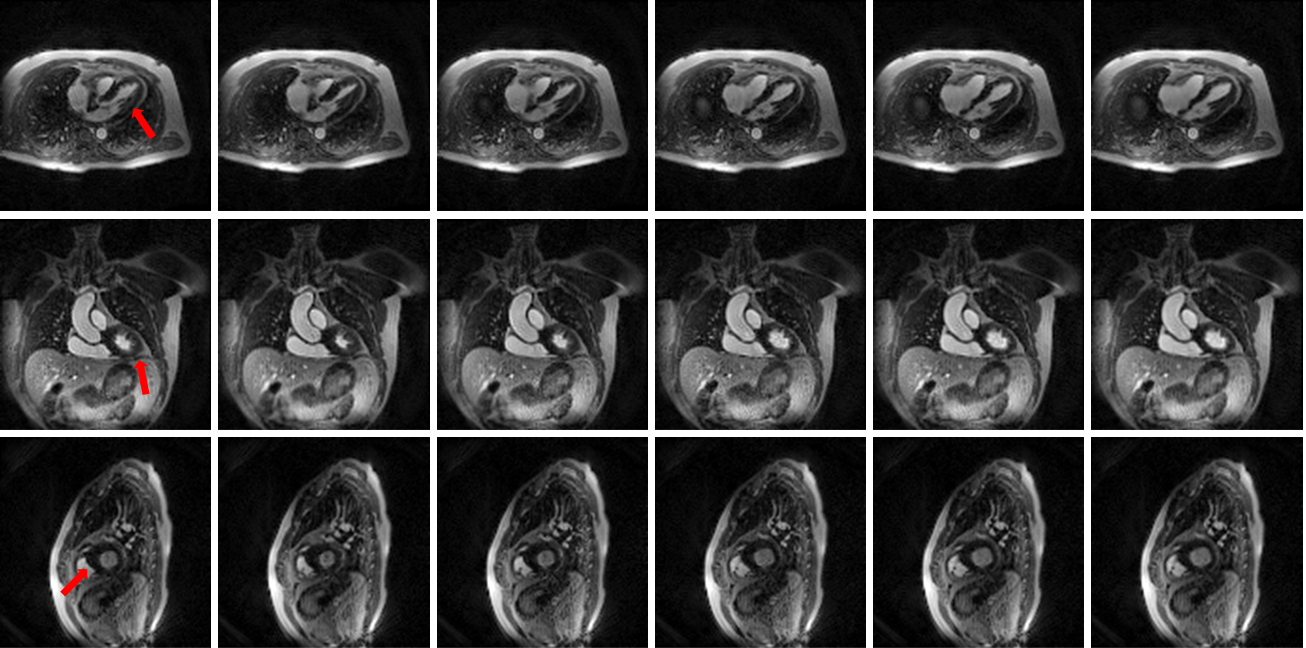

Figure 2. Reformatted long-axis views (first two rows) and short-axis view (third row) over one cardiac cycle, shown at the same temporal resolution as in Figure 1 (only 6 of the 12 reconstructed frames are shown). The reconstructed cine frames clearly demonstrate soft tissue contrast, including visualization of the papillary muscles and myocardium, while capturing free-breathing cardiac and respiratory motion.